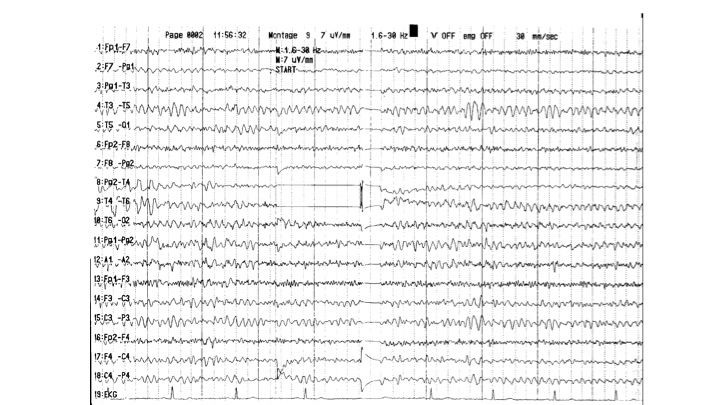

Artefakte im EEG | 62.65 zurück | weiter